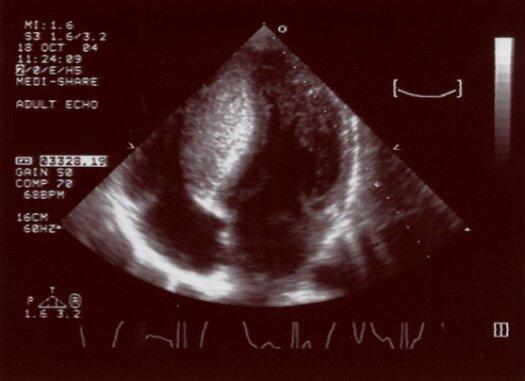

Although voltage criteria for LVH apply above the age of 40, large QRS voltage in young individuals is strongly suggestive of hypertrophy. Echocardiogram (panel below) showed hypertrophic cardiomyopathy with marked septal hypertrophy (2.6 cm), but no resting gradient in the left ventricular outflow tract.

Echocardiogram